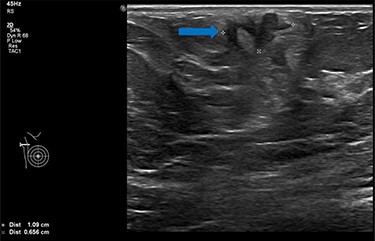

She underwent triple assessment. Bilateral mammogram showed no abnormality in either breast. However, right axillary accessory breast tissue had notably increased in size since her previous mammogram (7 months earlier) and displayed slight distortion (R3) (Fig. 1). Ultrasound scan of the right axilla showed accessory breast tissue measuring 56 × 50 mm in its maximum dimension without any abnormal axillary lymph nodes. Furthermore, the palpable lump showed indeterminate characteristics (U3) measuring 10.9 × 8.3 mm (Fig. 2). Ultrasound-guided core biopsy of the abnormality showed Grade 1 mucinous adenocarcinoma (Fig. 3) which was oestrogen and progesterone receptor positive (Quick score of 8) and Her-2 negative. There was no evidence of lymphoid tissue in the core biopsy.

Ultrasound scan of right axillary accessory breast tissue shows focal area of illdefined hypoechogenicity underlying the dermis measuring 10.9 × 8.3 mm (blue arrow). No associated significant hypervascularity. The imaging appearance are indeterminate, U3 (Royal College of Radiologist, Breast Group Classification).